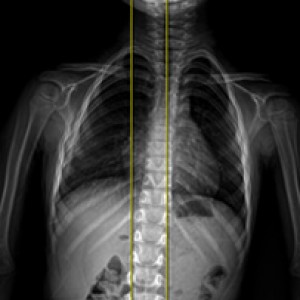

근육과 근막의 정렬을 함께 진단하며, 풀 스파인 촬영을 통해 머리부터 모든 고관절, 발의 정렬까지 함께 파악하여 개개인에 맞는 전신 치료법을 설계합니다.

전신 엑스레이 검사